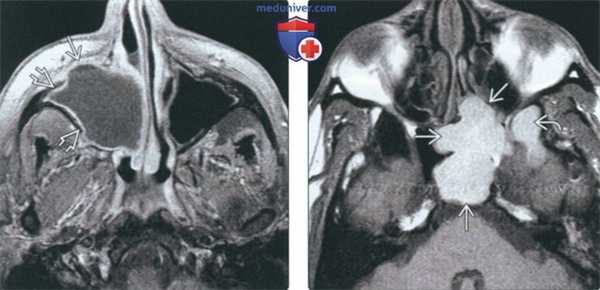

(Слева) При аксиальной МРТ Т1ВИ С+ FS определяется мукоцеле правой верхнечелюстной пазухи с эрозиями передней стенки и распространением кнутри в полость носа. Определяется также периферическое контрастирование слизистой оболочки, но без накопления контраста в центре, что помогает отличить мукоцеле от новообразования.

(Справа) При аксиальной МРТ Т1 визуализируется мукоцеле большого размера в левой основной пазухе, относительно гиперинтенсивное из-за белкового содержимого. Обратите внимание на поражение латерального кармана.

(Слева) На аксиальной МРТ (Т1 ВИ С+ FS) определяется мукоцеле правой верхнечелюстной пазухи с эрозией передней стенки и распроаранением в полость носа. Слизиаая оболочка на периферии накапливает контраст, что помогает отличить мукоцеле от новообразования.

(Справа) На аксиальной МРТ (Т1 ВИ) определяется большое мукоцеле правой сфеноидальной пазухи с однородным гиперинтенсивным сигналом, обусловленным большим содержанием белка. Обратите внимание на вовлечение бокового кармана.